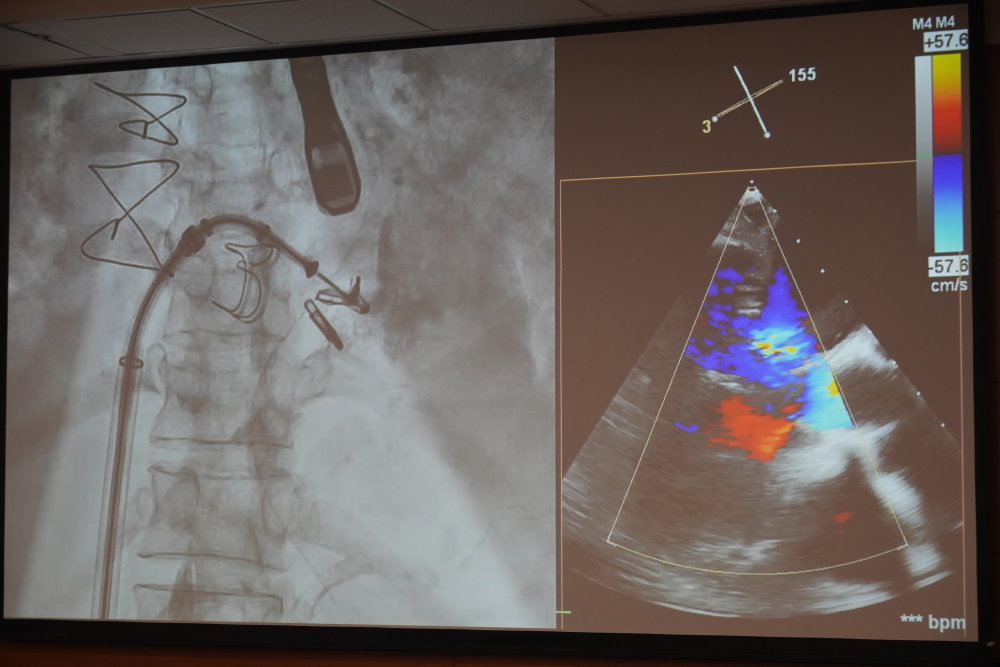

75歲的張女士日前因急性心肌梗塞緊急就醫,雖經心導管手術打通血管,卻突發嚴重呼吸困難。檢查發現她合併急性二尖瓣逆流(acute MR),導致肺水腫與呼吸衰竭,無法自行呼吸。成大醫院心臟血管科黃睦翔醫師指出,張女士因心肌梗塞引發急性瓣膜功能惡化,若進行傳統開胸手術,風險極高,最終團隊決定採行經導管二尖瓣修補術(Transcatheter Edge-to-Edge Repair, TEER)。手術成功減少逆流,肺水腫也快速緩解,順利拔管出院,可正常活動,目前持續門診追蹤中。